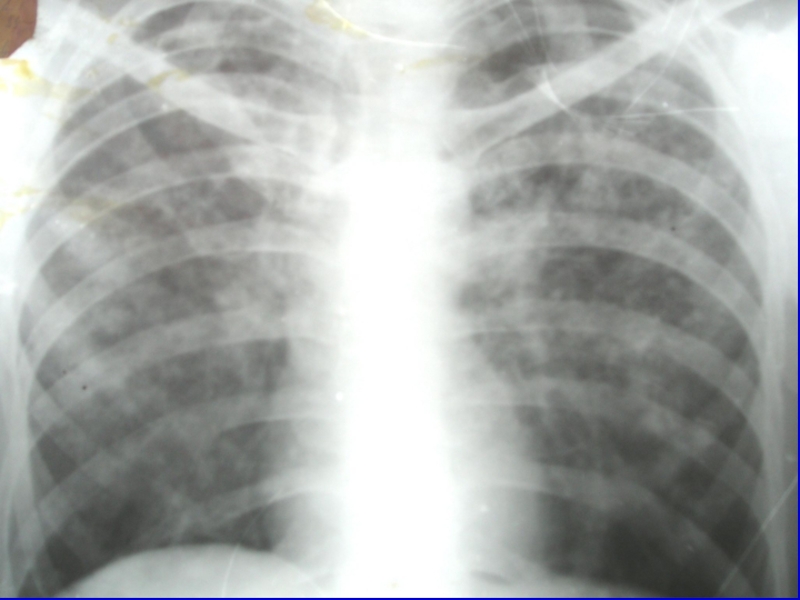

Острый милиарный туберкулез Рентгенологическая картина

Рентгенологическая картина острого милиарного туберкулеза

легких в первые дни заболевания характеризуется диффузным понижением прозрачности легочных

полей, а затем появляются симметрично множественные округлой формы нерезко очерченные очаги, величиной до просяного зерна.

Слайд 14Острый милиарный туберкулез Рентгенологическая картина

характеризуется наличием мелких мягких очагов

(1-2 мм) одинаковой величины, расположенных симметрично в над- и подключичных

зонах, преимущественно в кортикальных слоях легких (эксудативного характера).